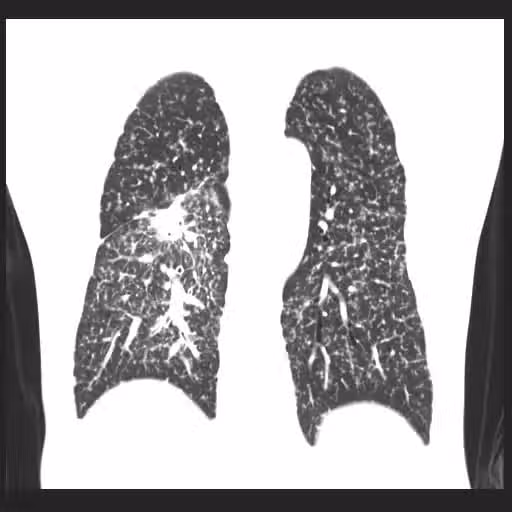

媽媽、2個兒子全肺癌!他一查末期... 醫嘆「用這清潔劑」等於抽20支煙 #3電器也上榜

圖片來源:蘇一峰臉書

他建議,病患家屬最好在親人「診斷出肺癌的年齡提前10歲」做篩檢,目前最有效的檢測方式是「低劑量電腦斷層」篩檢,如果肺部乾淨沒有結節,那麼往後3至5年都算安全。另外,蘇一峰也提醒,想要遠離致癌因子,除了油煙、二手煙、空污外,使用家中電器、公司印表機時,也要特別注意...